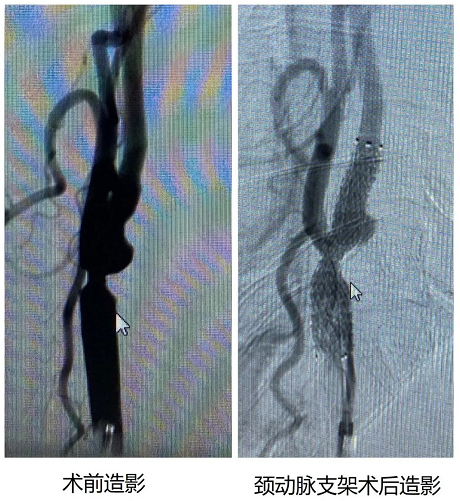

手术当日,心血管科田伟主治医师首先为孙大爷植入了临时起搏器,保证了心率、血压稳定。随后,针灸科/神经内科/康复科刘桂林主任医师、王少松副主任医师、姬旭主治医师为患者进行了全脑血管造影,并顺利植入了右颈动脉自膨式支架一枚,整个手术过程顺利,术后孙大爷安返病房,目前正在积极康复当中。